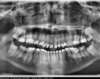

Radios de fin